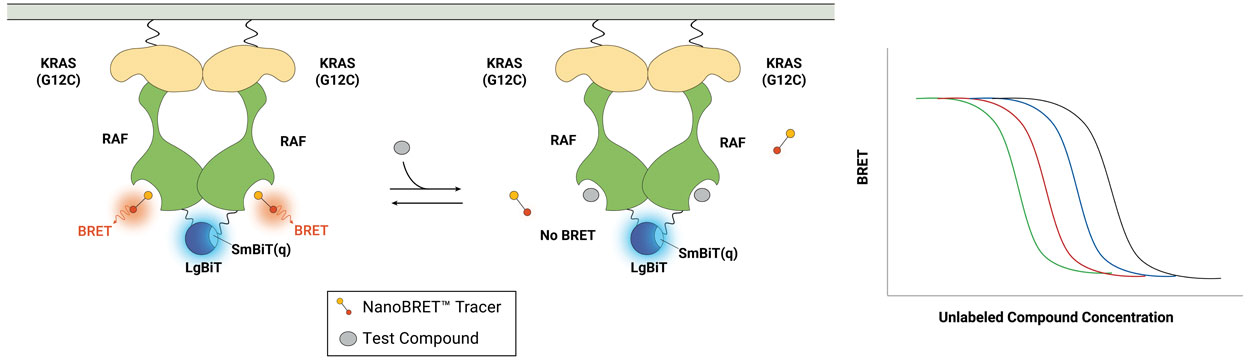

NanoBRET® technology offers a sensitive, specific method to measure the interaction of small-molecule drugs with their target protein in live cells.

With the NanoBRET® Target Engagement Assay, you can:

- Quantitate compound affinity (how tightly it binds to a protein) and target protein occupancy (how much compound binds to a protein) in live cells.

- Assess how long a compound binds to the target protein (its residence time) under physiological conditions.

- Scale the simple, multiwell assay to suit your research throughput needs.

- Generate high‐quality data with low error rates and high reproducibility.

- Get started quickly with available ready-to-use assays.

Principle of the NanoBRET® Target Engagement Assay.

Measure TE on Intracellular RAS Complexes

The NanoBRET® TE Intracellular RAS Assay measures intracellular compound binding to RAS proteins with ready-to-use assays for quantify compound affinity and fractional occupancy for multiple RAS variants, including KRAS, HRAS and related hot-spot mutants. Utilizing NanoLuc® Binary Technology (NanoBiT) complementation to create the energy donor enables the measurement of cellular target engagement on multimeric RAS complexes to more accurately reflect RAS biology. Measure engagement for individual RAS complexes or profile compound selectivity across RAS variants.